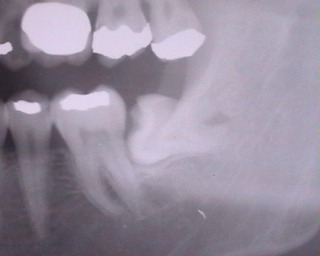

会社そばの歯医者さんに電話して歯が痛いので予約。当日、歯医者に行ってレントゲンを取って診察してもらいました。原因は横に伸びた親知らずですね。虫歯はありませんので次回、親知らずを抜きましょう。いつにしますか?

歯医者さん複雑なので葉を砕いて抜歯します30分でいけます

歯医者さんにどれぐらいかかりますか?半分以上埋没しているので歯を砕いて取り出します。抜歯から歯茎を縫い合わせるのまで入れて30分で出来ますよ。っと言われて、自分としては、え?30分なんだ大したことないじゃんっと感じてしまいました。

自分の場合はかなり奥にあったんですが、紙一重で上顎洞(じょうがくどう)の副鼻腔と親知らずが肉の壁ギリギリで助かったのでよかったと言われました。